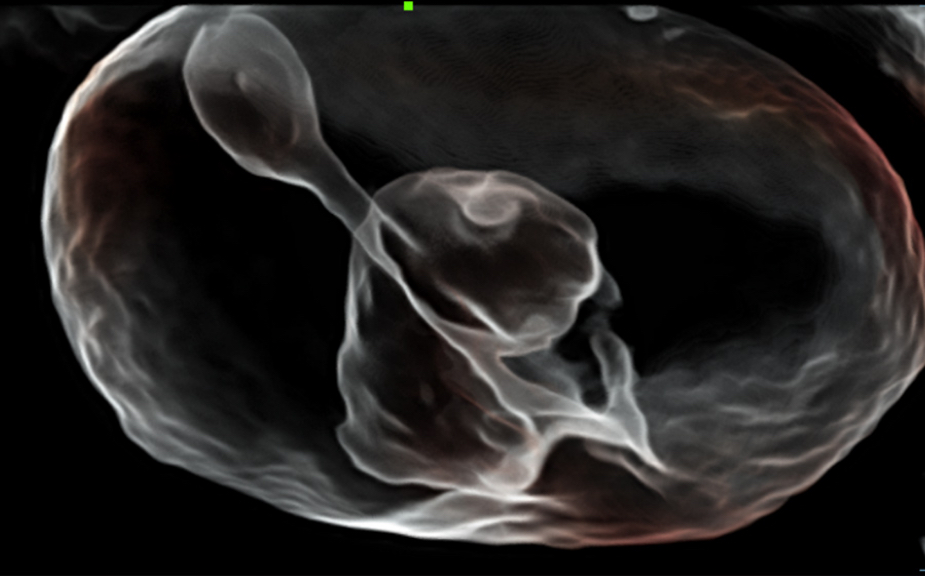

Le Nuewa?I9, con?u spÃĐcialement pour la santÃĐ de la femme et les soins nÃĐonataux, offre une expÃĐrience entiÃĻrement nouvelle gr?ce aux innovations dont il est dotÃĐ, tant à lâintÃĐrieur quâà lâextÃĐrieur. Ces innovations sont dÃĐveloppÃĐes sur la base d'une comprÃĐhension approfondie de scÃĐnarios cliniques complexes, fournissant des rÃĐponses prÃĐcises et adaptÃĐes ainsi qu'une efficacitÃĐ exceptionnelle et une expÃĐrience utilisateur remarquable.

La plate-forme ZST+?est une innovation extraordinaire, reprÃĐsentant une ÃĐvolution de lâimagerie ultrasonore. Elle transforme la formation conventionnelle de faisceaux en un traitement basÃĐ sur les canaux de donnÃĐes. Elle repousse les limites de lâimagerie conventionnelle et du compromis entre rÃĐsolution spatiale, rÃĐsolution temporelle et uniformitÃĐ tissulaire en offrant une qualitÃĐ dâimage exceptionnelle pour des solutions dâimagerie infinies et en constante ÃĐvolution.